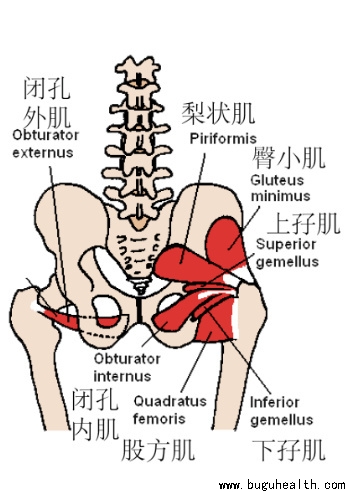

- 布骨医学科普:深入梨状肌,不只是髋关节外旋肌! BuGuRMC布骨康复医疗中心 ,2023-11-27

- 梨状肌是位于臀部深层的一对扁平肌肉,在运动训练的语境中,它常常被包含在一组被称为“髋外旋肌”的肌群之中。.....